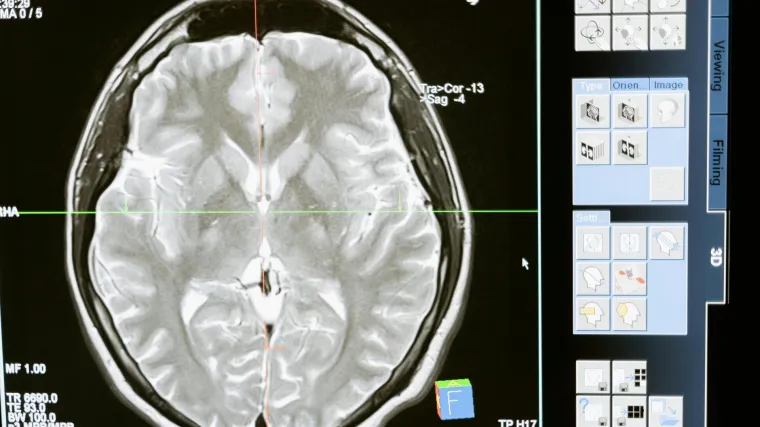

Ovo će promijeniti živote: Okrutna bolest koja ubija moždane stanice može se liječiti!

Ova teška bolest je rijetka te uzrokuje progresivno propadanje živčanih stanica u mozgu

Huntingtonova bolest je rijetka te pogađa oko pet od 100.000 ljudi, a uzrokuje progresivno propadanje živčanih stanica u mozgu. Utječe na kretanje, kognitivne sposobnosti i emocije osobe te se s vremenom pogoršava.

Kod Huntingtonove bolesti, genska mutacija pretvara normalni protein potreban u mozgu (nazvan protein huntingtin) u ubojicu neurona. Novi tretman djeluje tako što trajno smanjuje razinu toksičnog proteina korištenjem genetske medicine koja kombinira gensku terapiju i tehnologije utišavanja gena.